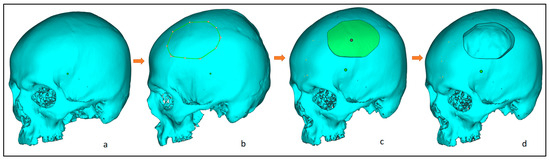

2.2. Customized Implant Design